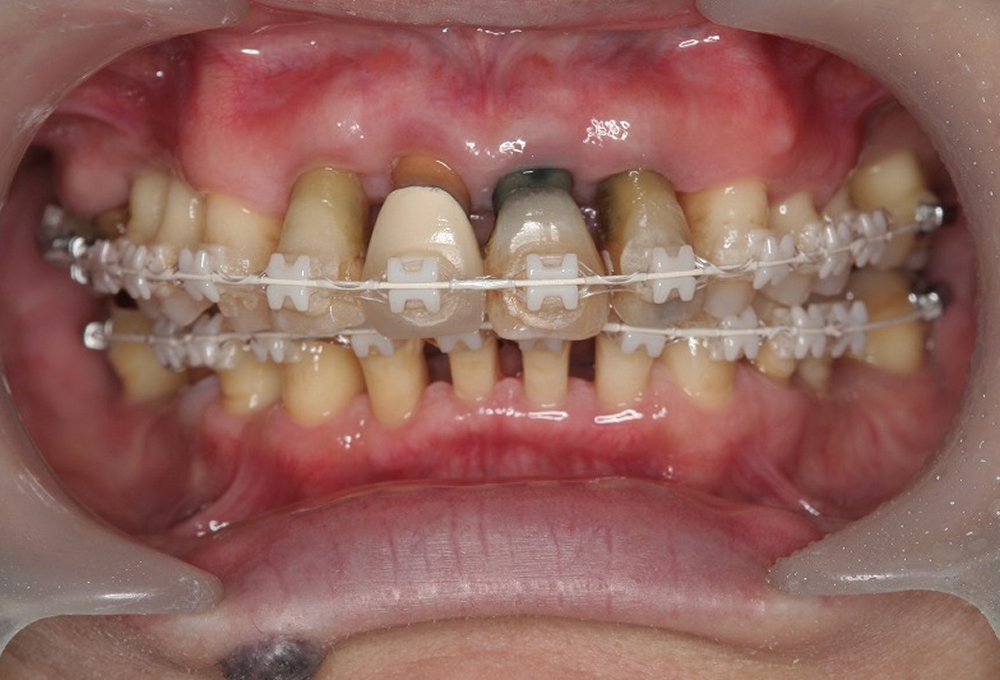

⑥矯正中